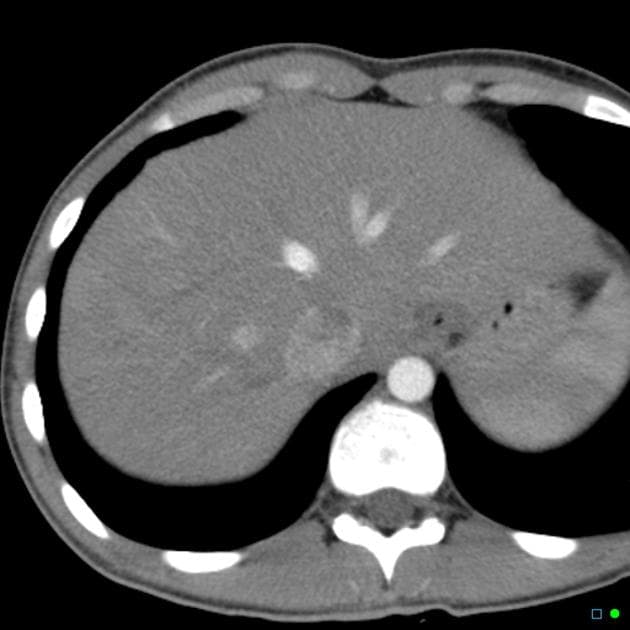

- 1.Vết rách gan kèm máu tụ dưới vỏ

- 2.Tổn thương nhu mô gan với thoát thuốc cản quang hoạt động

- 3.Tổn thương mạch trung tâm liên quan tĩnh mạch gan hoặc nhánh cửa

- "Hệ thống phân độ chấn thương gan AAST 2018 kết hợp cả dạng tổn thương hình thái và mức độ liên quan mạch máu để phân loại chính xác hơn."

- "Độ I–III biểu hiện các vết rách hoặc máu tụ ngoại biên, trong khi độ IV–V liên quan tổn thương nhu mô trung tâm hoặc chấn thương mạch máu lớn."

- "Thoát thuốc cản quang hoạt động trên CT là dấu hiệu hình ảnh quan trọng cho thấy chảy máu đang diễn ra và có thể ảnh hưởng đến quyết định điều trị."